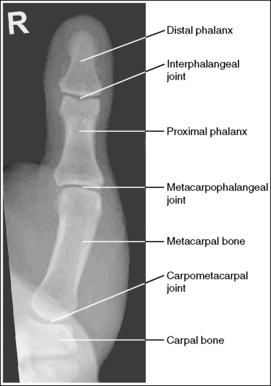

See Figures 4-12 and 4-13 and Box 4-5.

The first digit demonstrates an AP projection. The concavity on both sides of the phalangeal and metacarpal midshafts is equal, as is soft tissue width on both sides of the phalanges.

• An AP projection is accomplished by internally rotating the patient's hand until the thumb is positioned in an AP projection (Figure 4-14). The thumbnail can be used as a reference to determine when the thumb is truly placed in an AP projection. The nail should be positioned directly against the IR and should not be visible on either side of the thumb. A nonrotated AP thumb projection demonstrates equal concavity on both sides of the phalangeal and metacarpal midshafts, as well as equal soft tissue widths on both sides of the phalanges.

The long axis of the thumb is aligned with the long axis of the collimated field.

The IP, MP, and carpometacarpal (CM) joints are visible as open joint spaces, and the phalanges are not foreshortened.

• The IP, MP, and CM joint spaces are open, and the phalanges are demonstrated without foreshortening as long as the thumb is positioned flat against and placed parallel with the IR and the central ray was perpendicular to and centered with the MP joint space. This positioning aligns the joint spaces parallel with the central ray and perpendicular to the IR and positions the long axes of the phalanges perpendicular to the central ray and parallel with the IR. These relationships change when the thumb is flexed or posteriorly extended (hitchhiker's thumb) for the image. Thumb flexion and extension foreshorten the phalanges and superimpose them over the joint spaces (see Image 12).

Superimposition of the medial palm soft tissue over the proximal first metacarpal and the CM joint is minimal.

• Minimal soft tissue overlap occurs when the medial palm surface is drawn away from the thumb. It may be necessary to use the patient's other hand as an immobilization device to maintain good positioning of the medial palmar surface. If the medial surface of the palm is not drawn away from the thumb, the soft tissue and possibly the fourth and fifth metacarpals obscure the proximal first metacarpal and CM joint (see Image 13).

The MP joint is at the center of the exposure field. The distal and proximal phalanges, the metacarpal, and the CM joint are included within the collimated field.

• Center a perpendicular central ray to the MP joint, which is located where the palm's interconnecting skin attaches to the thumb, to place it in the center of the image. Open the longitudinal collimation to include the distal phalanx and CM joint. Transversely collimate to within 0.5 inch (1.25 cm) of the thumb skin line.